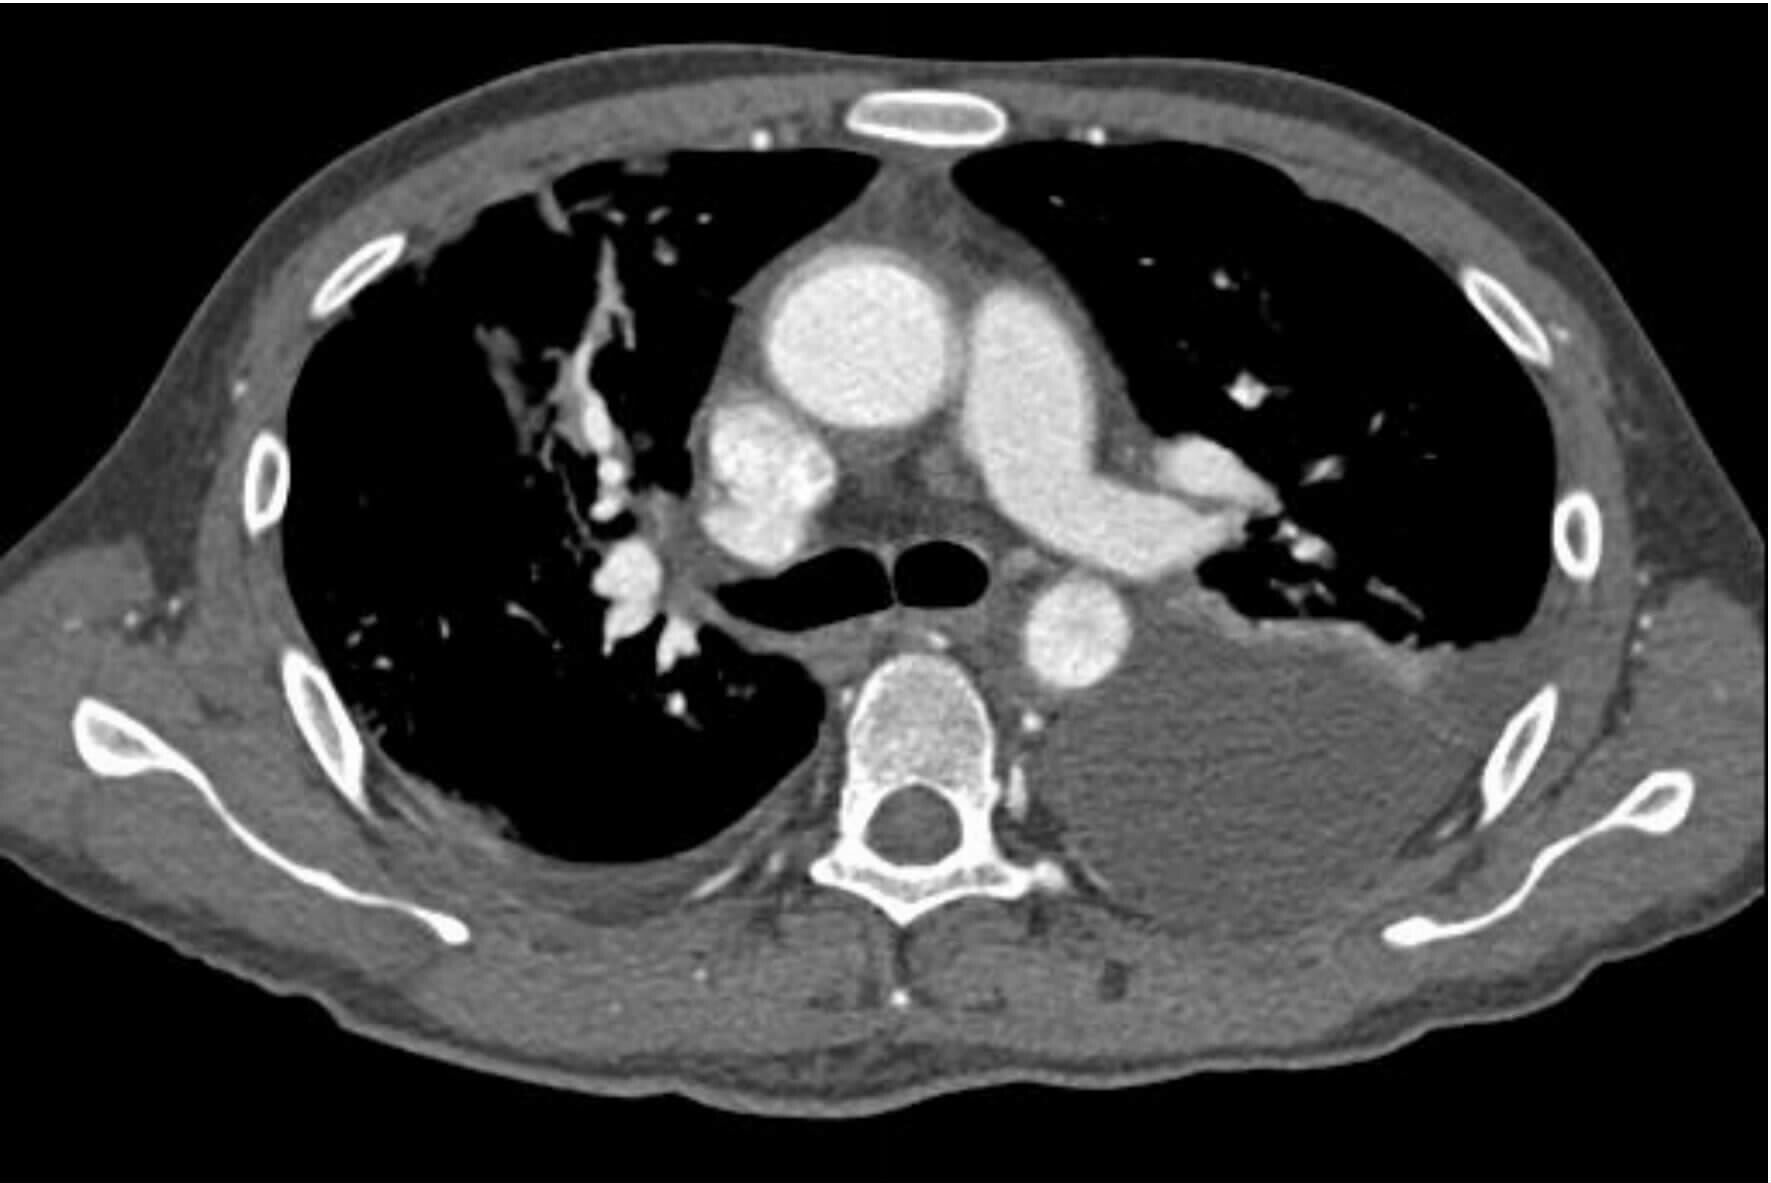

2 结果37例钝性胸主动脉损伤,CTA征象表现为内膜瓣、轮廓异常、血栓、动脉收缩、假性动脉瘤、主动脉夹层6种情况。①内膜瓣:内膜瓣为增强的主动脉管腔内可见一个或多个弧形弱化区(图 1)。②主动脉轮廓异常:表现为主动脉管壁或轮廓不规则,圆形的主动脉横切面发生变化,(图 2)。③假性动脉瘤:指主动脉壁破裂出血,形成主动脉壁外的血肿,主动脉管腔与不规则瘤腔结合处呈锐性边缘(单侧或双侧),(图 3)。④主动脉夹层:内膜片和主动脉真假两腔形成是诊断夹层动脉瘤的基本征象。内膜片将血管分为真假两个腔隙。增强早期真腔密度高于假腔,随时间延迟,假腔密度逐渐增高,假腔密度可等于或高于真腔,(图 4)。⑤动脉收缩表现为损伤节段主动动脉直径小于正常节段动脉直径(图 5)。⑥血栓;主动脉腔内息肉样低密度区(图 6)。本组37例钝性胸钝性胸主动脉损伤患者,CTA征象存在内膜瓣34例(91.8%),主动脉轮廓改变或腔异常37例(100%),动脉收缩17例(45.9%),主动脉夹层10例(27.0%),假性动脉瘤21例(56.7%),血栓1例(2.7%)。

| 图 1 主动脉峡部损伤内膜瓣征象 Figure 1 Intimal flap sign of aortic isthmus injury |